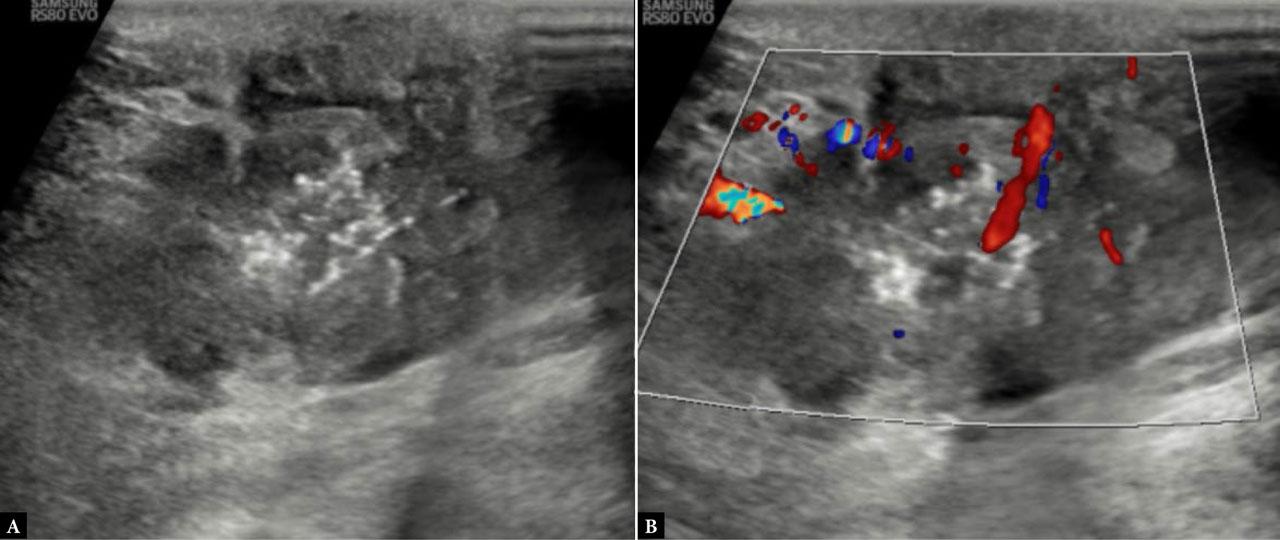

Fig. 3.